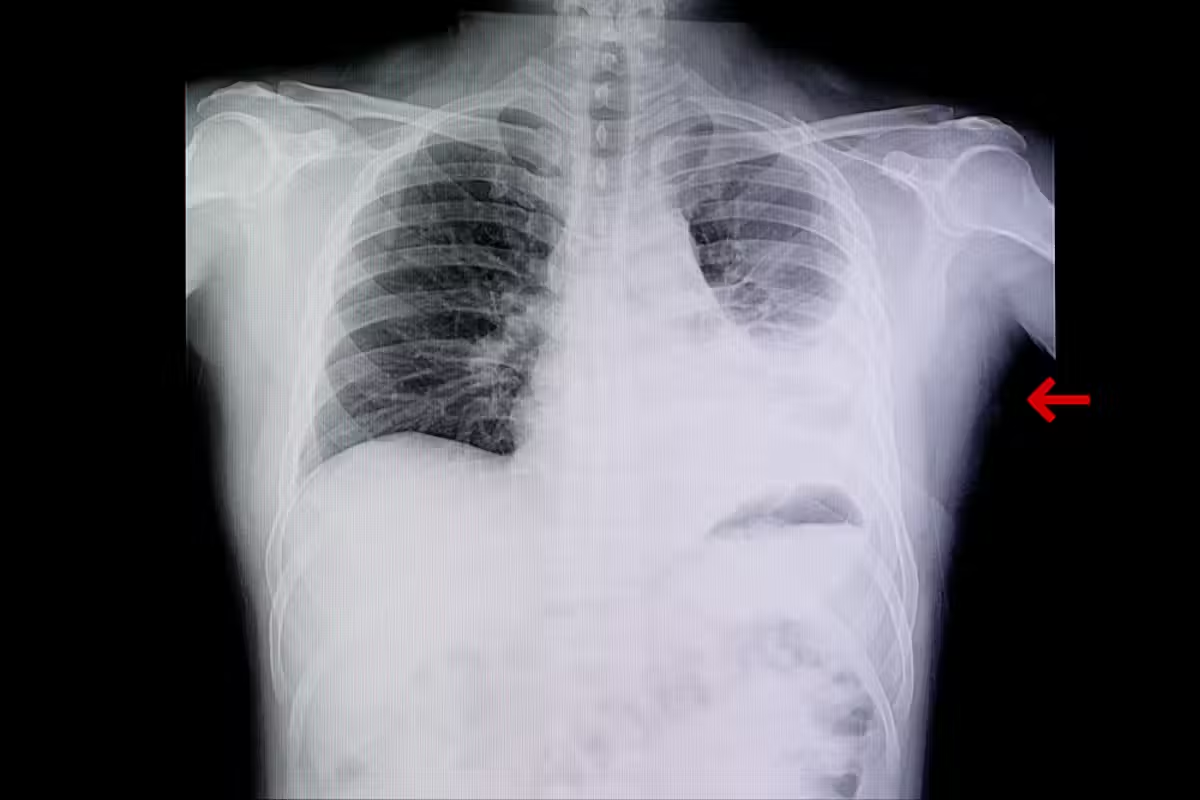

Knowing what a normal chest X-ray looks like is key to spotting health issues. A normal chest film shows dark lungs without any problems, a heart that’s the right size, and bones that look good.Detailed guide explaining all the key anatomical features and appearance of a thorax x ray normal view for review.

Density and Contrast in Normal Images

The density and contrast in a normal thorax X-ray are vital for spotting different body parts. Density shows how dark or light an area looks on the X-ray. Air-filled parts like the lungs show up black, while bones appear white because they are denser. Soft tissues, like organs, show up in shades of gray.

Contrast helps us see the differences between these parts. It’s what lets us see the lung borders and other internal details clearly.

Several important landmarks are seen on a normal thorax X-ray. These include the heart, diaphragm, rib cage, and clavicles. The heart should take up less than half of the chest’s width, with clear right and left sides.

Normal Lung Fields on X-Ray

When we look at a chest X-ray, the lung fields are key. These areas show where the lungs are and tell us about lung health.

Expected Lung Density and Transparency

Normal lungs look dark or lucent on an X-ray because they’re full of air. Their density is even, making them look more transparent than the heart and rib cage.

Normal Lung Markings and Vasculature

Lung markings, mainly blood vessel shadows, are seen in the lung fields. They’re more visible in the inner parts and at the lung bases. The lung’s blood vessels should be symmetrical and get smaller towards the edges.

Lung field extension is a sign of lung health. On a normal X-ray, lungs should go from the top to the costophrenic angles. They should also be symmetrical. Any difference means there might be a problem.

Healthy lungs are darker on the image, with clear markings at the lung field edges. This is what normal lungs look like on an X-ray.